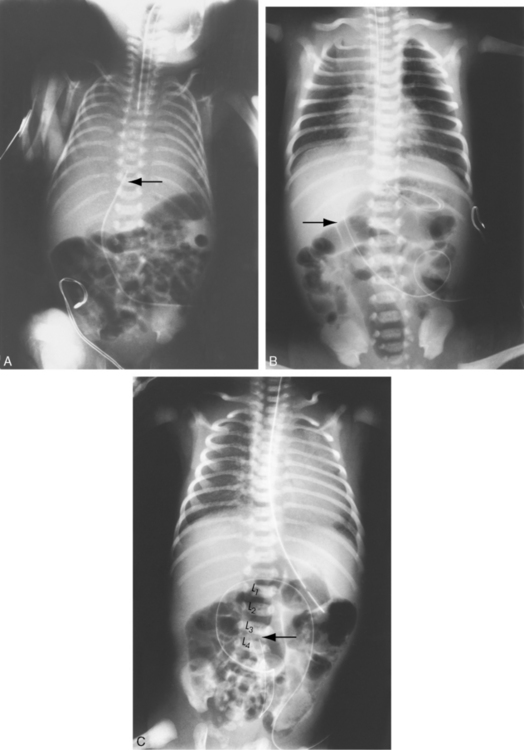

The newborn with diaphragmatic hernia may demonstrate severe respiratory distress. The chest radiograph reveals multiple abnormal air lucencies within the chest, usually the left hemithorax. This air is caused by the presence of loops of air-filled bowel in the chest (Fig. 10-6). The bowel compresses the lung on the involved side and shifts the mediastinum to the noninvolved (usually right) hemithorax, compressing that lung. Until the bowel fills with swallowed air, the newborn with a diaphragmatic hernia may be thought to have a mass in the left chest.

image image

Fig. 10-6 Congenital diaphragmatic hernia. A, This chest radiograph was obtained to evaluate a newborn admitted within the first few hours of life to the pediatric critical care unit with respiratory distress and poor feeding. The nasogastric tube can be traced into the left chest (arrow). The mediastinal structures are shifted to the right, and the dense opacity in the left hemithorax is due to the fluid filled stomach and loops of small bowel. There is no air in the stomach or small bowel. The newborn has a left congenital diaphragmatic hernia. B, This is a 2-day-old infant with a left congenital diaphragmatic hernia. There are multiple air-filled loops of bowel in the left hemithorax (arrows), with a marked shift of the mediastinum to the right. Note that in this case the nasogastric tube ends in the left upper quadrant of the abdomen, indicating that the stomach is in the abdomen and not in the chest.

(B, Radiograph courtesy of Sharon Stein, Nashville, TN.)